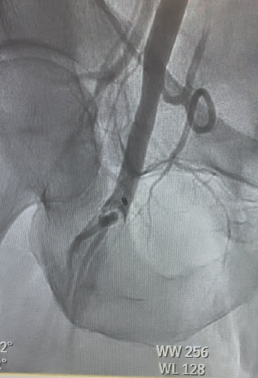

On arrival to our center, the patient continued to report chest pain (5/10). Troponin I had peaked to 31 ng/mL, and serum lactic acid was elevated. Repeat ECG showed resolution of ST elevations, but clinical suspicion remained high for cardiogenic shock. The patient was intubated and mechanically ventilated, and a periprocedural Impella 2.5 left ventricular assist device was inserted for circulatory support. Angiography confirmed left anterior descending (LAD) patency but with significant thrombus burden (Figure 1). Coronary mechanical thrombectomy was performed using the CAT RX catheter. Lesion preparation was carried out with a 4.0 x 12 mm Shockwave balloon at the ostial LAD, followed by deployment of a 4.0 x 18 mm drug-eluting stent extending from the ostial to the proximal LAD. The following day, the patient demonstrated significant clinical improvement, with an ECG showing normalization of ventricular function and ejection fraction. Following removal of the Impella, homeostasis was achieved; however, the right lower extremity appeared dusky with an absence of palpable and Doppler-detectable pulses.

Urgent intervention was undertaken. Left femoral access was obtained, and a 6F sheath was inserted for up-and-over access. A 5F Omni™ Flush catheter (AngioDynamics) was advanced into the right external iliac artery, and angiography revealed thrombus surrounding the previously placed MANTA closure device (Teleflex®). The catheter was exchanged for a 7F, 45-cm Pinnacle sheath (Terumo), and a 7F Lightning Bolt® aspiration catheter (Penumbra) was advanced for clot retrieval. The thrombus “lollipopped” onto the catheter; therefore, the entire aspiration system, including the sheath, was removed. A significant amount of clot was extracted (Figure 2).